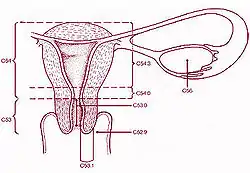

Image showing different structures around and relating to the human uterus | |

Additional images

14. Uterus: Parts: 15. Cervix; 16. Body and 17. Fundus. 18. Orifices: External and Internal; 19. Cervical canal; 20. Uterine cavity; Layers: 21. Endometrium; 22. Myometrium and 23. Perimetrium

24. Fallopian tube

30. Ovary

31. Visceral pelvic peritoneum: 32. Broad ligament (with 35. Mesometrium)

Ligaments: 36. Round

Blood vessels: 40. Uterine artery and veins

Other: 42. Ureter; 46. Internal iliac vessels (anterior branches); 48. Abdominal cavity

Schematic frontal view of female anatomy

Schematic frontal view of female anatomy